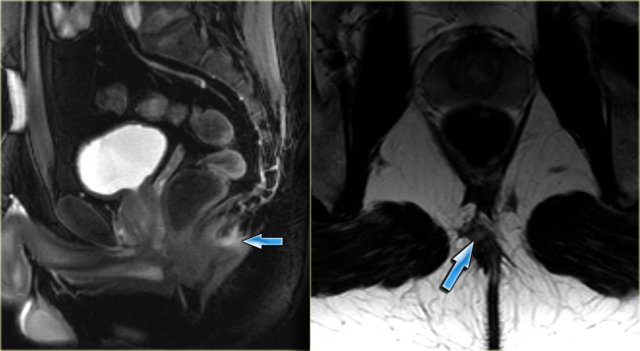

On the left an example of a suprasphincteric fistula.

There are two tracts in the ischioanal region.

The right sided tract runs over the puborectal muscle (asterisk) and the mucosal opening lies at the level of the linea dentata (black arrow).